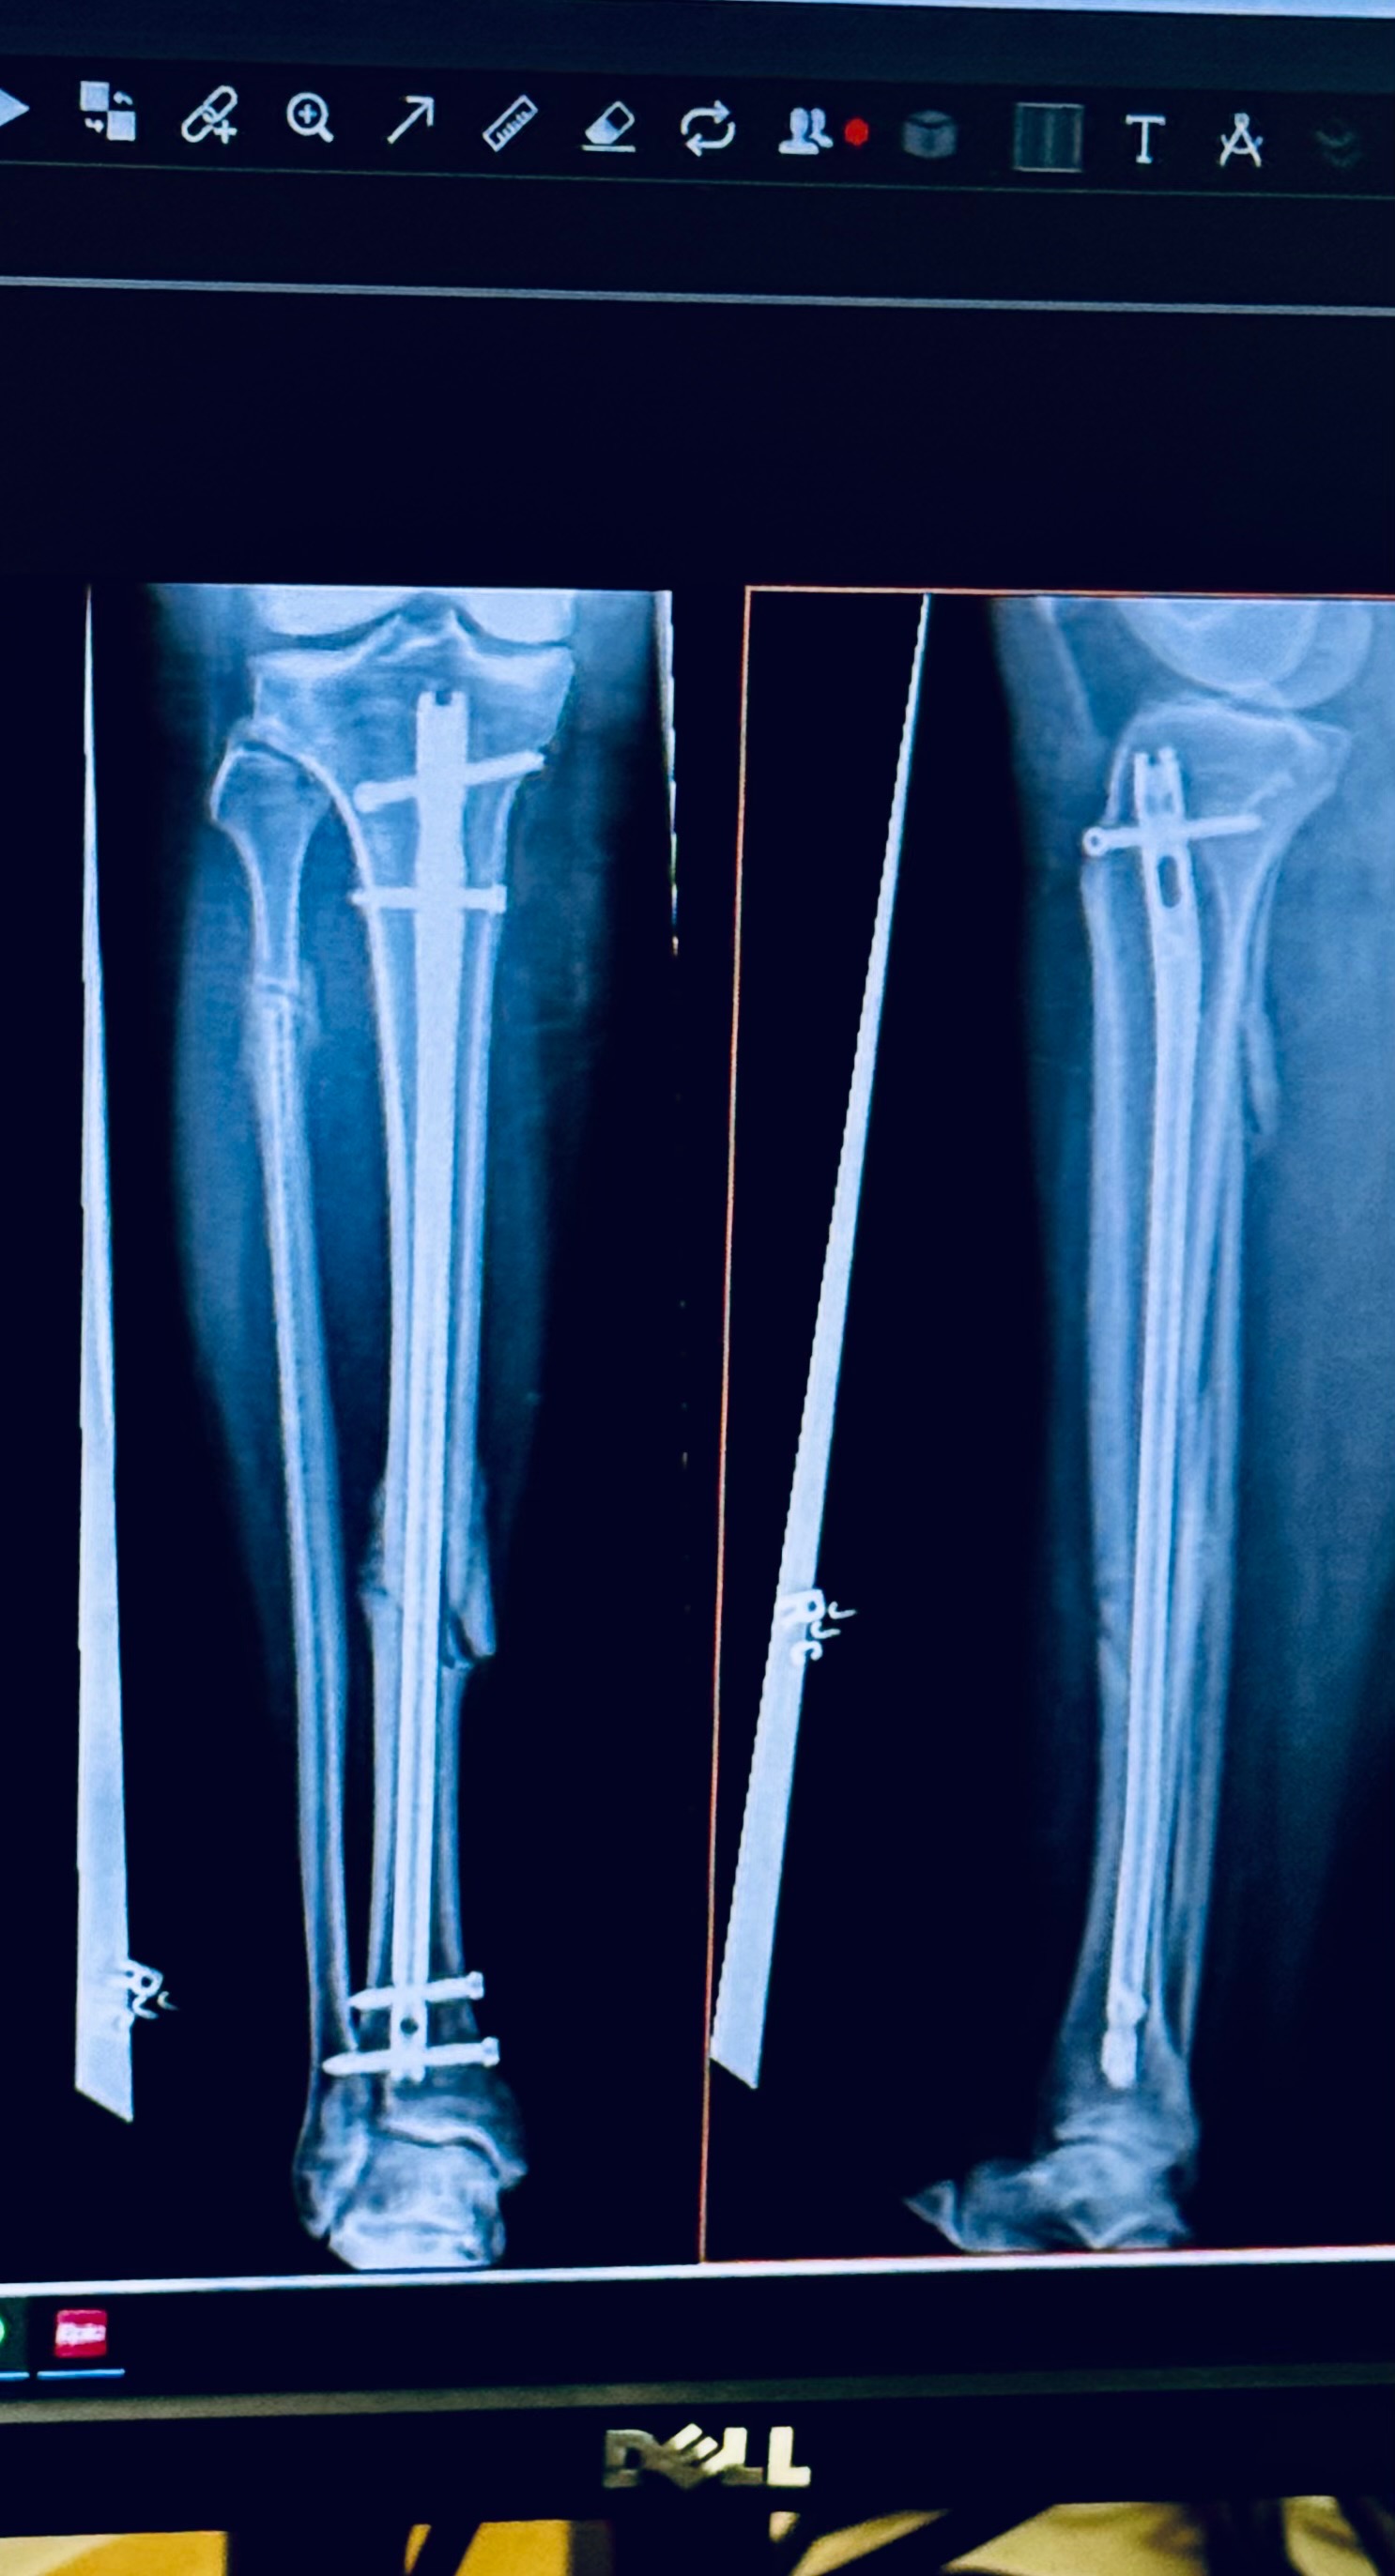

About 4 months ago, in a wildly freak accident, I broke both bones in my lower leg and one of those silly bones even came out of my skin. That day they reset my bones in the ED and the following morning, I had surgery to insert a rod into my tibia and screws to hold it in place in my ankle and knee. They also irrigated my leg to be sure no infection got into my bone that had made an appearance to the world.